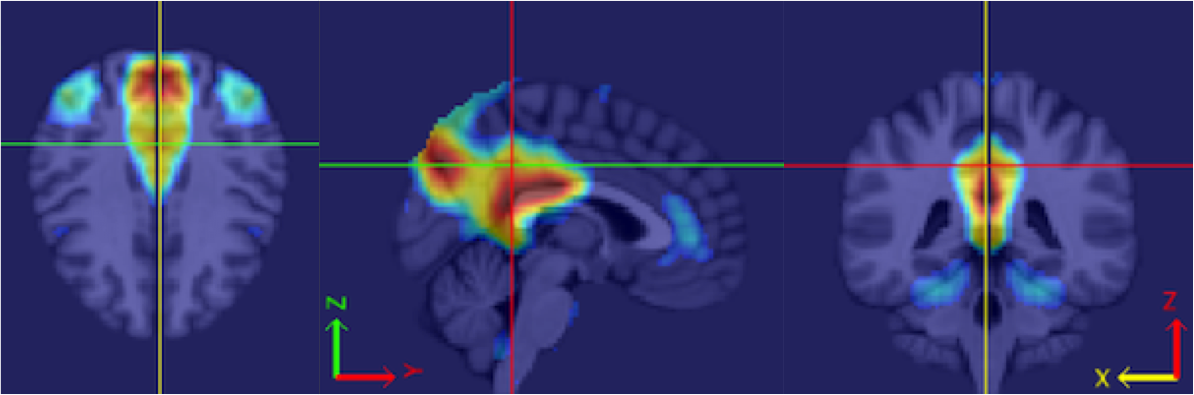

Caffo’s specialty is a kind of brain scan called “functional magnetic resonance imaging” — or fMRI for short. Unlike X-rays, which show only the brain’s structure, the colorful pictures created using fMRI show the brain at work. Neuroscientists are especially interested in seeing which parts of the brain light up (and which don’t) when someone does a particular task. This helps them map connections between different parts of the brain.

Caffo works at the Bloomberg School of Public Health at Johns Hopkins University in Baltimore. There, he separates real brain signals contained in fMRI images from meaningless static. Statistics provides the tools he needs to erase that confusing “noise.”

Using fMRI images for prediction poses a challenge, however. Usually, scientific theories relate one quantity (which we’ll call x) to another quantity (which we’ll call y). For example, how fast a person throws a ball (x)determines how far it will go (y). But what can be done when the values for x or y are not numbers, but pictures?

So far, the best solution has been to turn pictures into numbers. Doing that creates a lot of numbers. Think of the old saying: A picture is worth a thousand words. But with a single fMRI scan, a picture may translate into hundreds of thousands of numbers. Statisticians need fancy math to compress and process these data in ways that give scientists something meaningful.